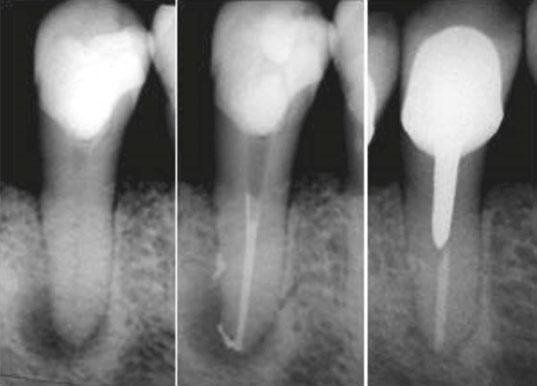

Figures 2-6: TrueTooth maxillary molar replica used from access to obturation and postendo restorative

4. Clear and opaque replicas are ideal for teaching mental imaging skills. Mental imaging is the most important skill a dentist brings to a root canal party, and while some of us have a natural ability in that regard, most of us need help figuring out how to do that. Training in clear replicas provides a view of exactly what is happening; for instance, when a rotary file is cutting through a curved canal, The best experience is to first do it in a clear replica and see it, then do the same procedure without directly seeing it in an opaque replica. Lots of “aha’s” happen with this teaching method. The results have been amazing (Figures 2-6).